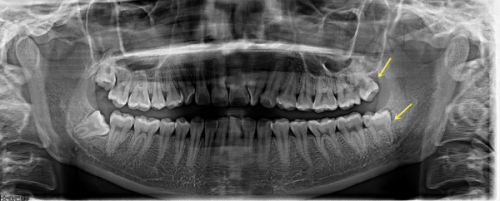

我第一次来到宁波牙博士口腔医院时,前台的工作人员非常热情地接待了我,引导我填写了相关的表格,并安排了医生为我进行初步的检查。医生仔细地询问了我的牙齿情况和病史,然后对我的口腔进行了全方面的检查。之后,医生建议我进行一些必要的检查,如口腔CT等,以确定我的牙齿状况和适合的种植牙方案。

宁波牙博士口腔医院的种植牙技术有着特别多特色。首先,医院采用了精良的数字化种植技术,通过口腔CT等设备获取患者口腔的严谨数据,然后利用计算机模拟种植过程,制定出更适合患者的种植方案。这种技术可以大大提高种植的正确性和成功几率,减少手术的创伤和风险。